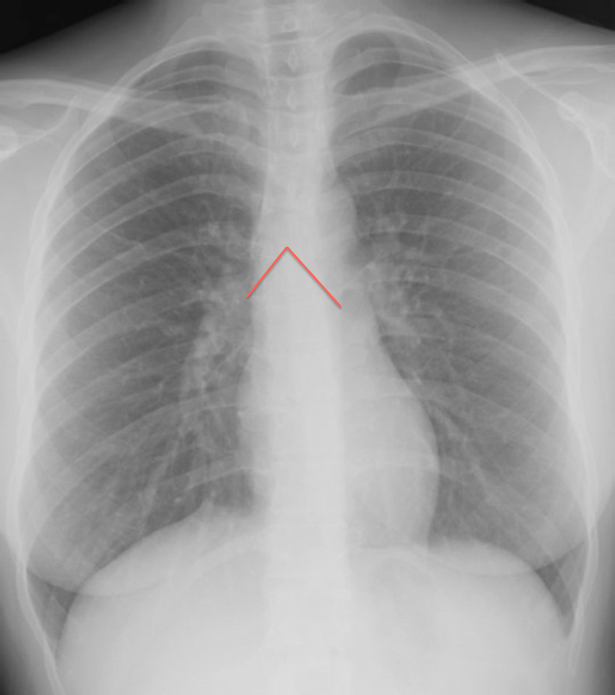

The other frustrating thing about dealing with chest x-rays is sometimes the radiologist tells you something is there that you can’t actually, you know, see. For instance, when you evaluate an X-ray, you have to identify the “carina” as an important point of reference. “Carina” is the fancy medical word for the point where your trachea branches off into the two bronchi, the main tubes supplying the lungs.

For orientation, here’s a cartoon of the carina:

The carina is where the pink tube splits in two, in case you’re like me and need everything explained like you’re five. It seems like you should be able to clearly pick this branch point out, right? Especially if you know roughly where it’s supposed to be. In lecture, Mr. Excited Radiologist demonstrated the branches with some helpful lines, which I have replicated here (same normal X-ray as before):

Do you see? No? Well, you should! Obviously the carina is right there for the taking, you idiots.

(I have looked at this x-ray until my eyes hurt. I see absolutely nothing. Maybe the carina is a mythical creation, like the PMI on the cardiac exam.